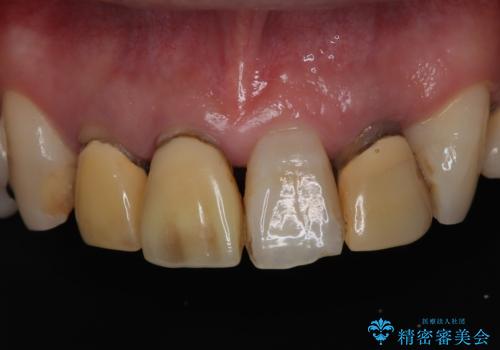

古い被せ物を除去しオールセラミッククラウンで治療を行いました。

- 495,000円(オールセラミッククラウンスペシャル154,000円×3本+仮歯11,000円×3本)費用は治療当時の料金となります

被せ物の適合が悪く劣化もおこし色が変色している状態でした。そのため他の歯とも色が合っていませんでした。古い被せ物を除去し形を整えた後にオールセラミッククラウンで治療を行いました。